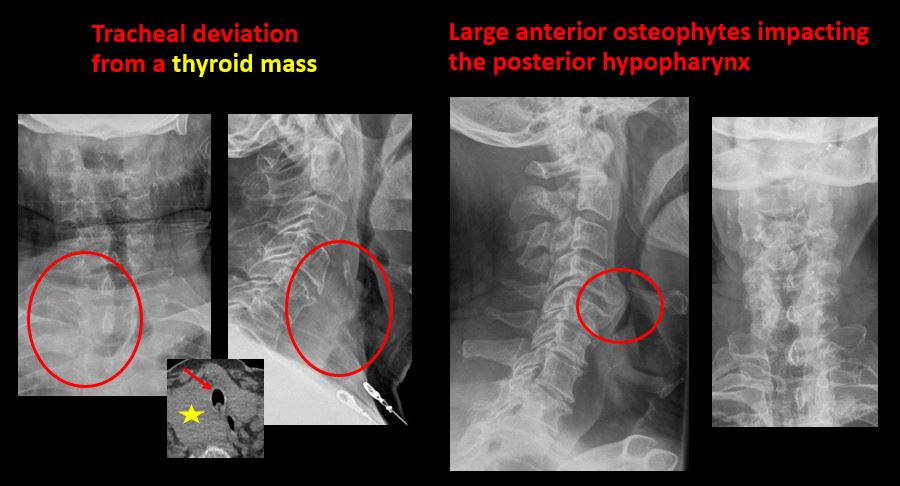

The airway is narrowed or displaced. [Yes/No]

There is calcification, foreign body, abnormal air, or other abnormal density in the prevertebral or paravertebral soft tissues. [Yes/No]

There is focal or diffuse abnormal mineralization. [Yes/No]